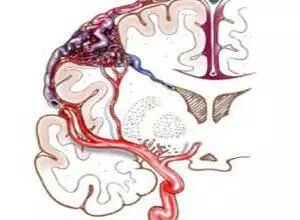

硬脑膜动静脉瘘,其实质是发生在“硬脑膜”及其附属结构上的“动静脉瘘”。动静脉瘘则是动脉血管和静脉血管之间的直接短路,可先天存在或因后天各种因素导致。

简单地说,所谓的硬脑膜动静脉瘘,就是缺少了毛细血管,动脉和静脉之间直接相连,发生在硬脑膜及附属结构上,动脉和静脉之间发生了短路。